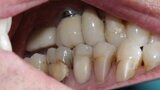

Figure 8 Right side in occlusion before treatment